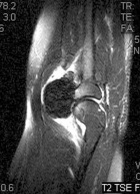

62 y/o female presents with a few months of an increasing left elbow mass, discomfort with activity, relieved by rest

PMH/PSH: Breast cancer treated with lumpectomy, nonsmoker

PE: Large nontender mass anterior L elbow, only a few degrees loss of ROM at elbow, no LAN, neurovasculary intact